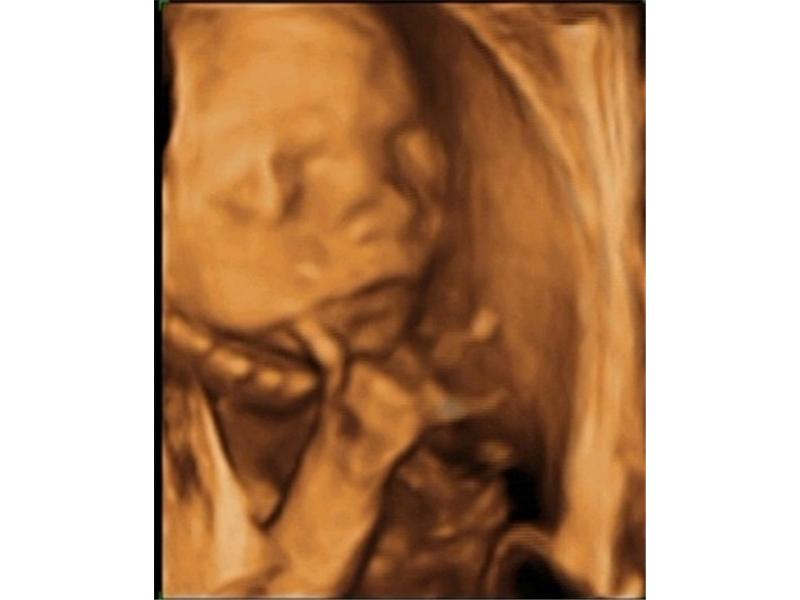

Kluk jako buk